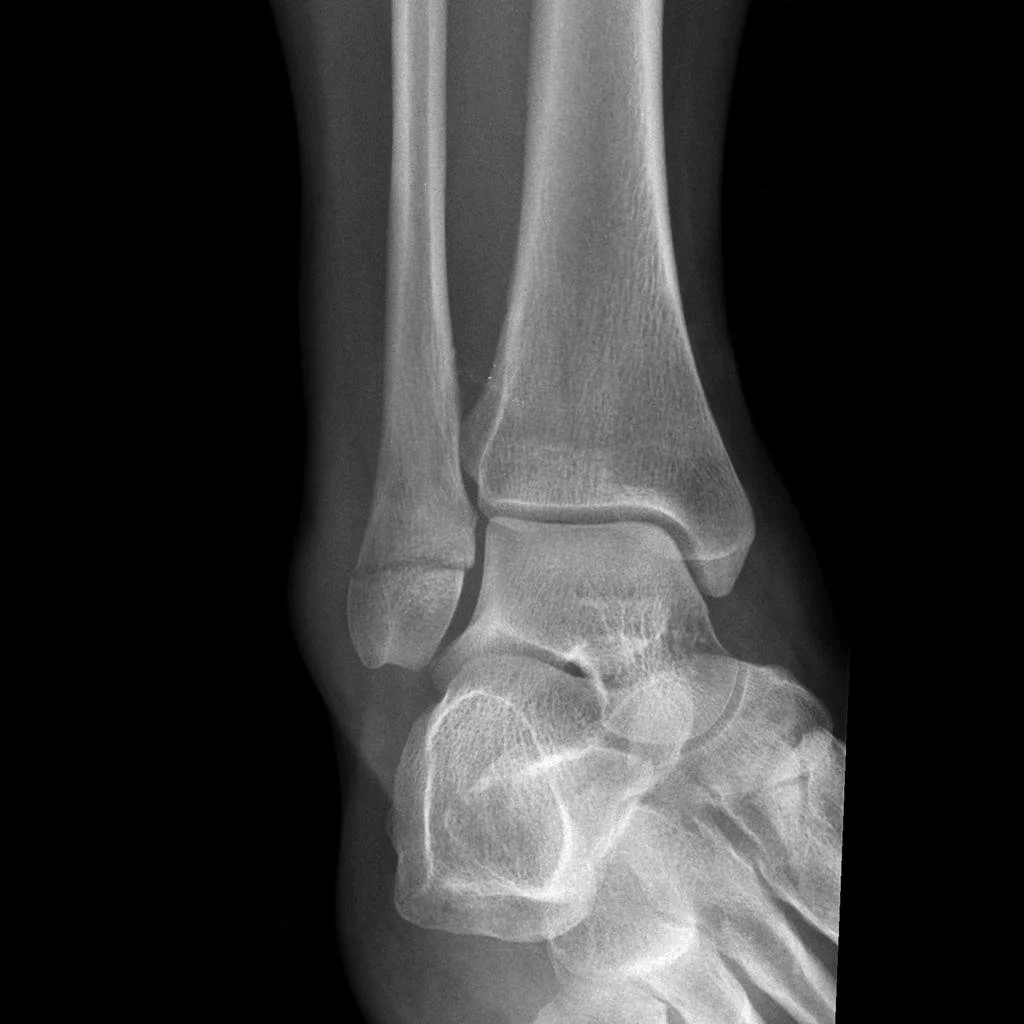

Do you need an XRAY after an Ankle Sprain?

Just sprained your ankle? Not sure if you need to get yourself to the hospital for an XRAY? Read on to find out how we determine if someone needs an XRAY or not after spraining their ankle.